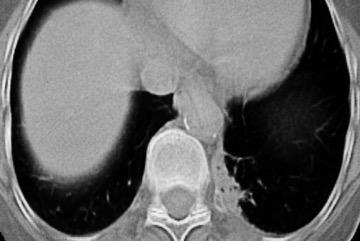

Parálisis frénica transitoria tras cirugía de válvula aórtica

Parálisis frénica transitoria post cirugía cardiaca (10%).

Puede acompañarse de atelectasia del LII.

Benjamin JJ et al. . Left lower lobe atelectasis and consolidation following cardiac surgery: the effect of topical cooling on the phrenic nerve. Radiology 1982